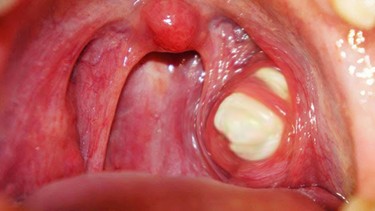

- Áp xe quanh amidan: Nhiễm trùng lan rộng hình thành ổ mủ quanh amidan, khiến người bệnh đau họng dữ dội, khó nuốt, thậm chí khó thở.

- Xuất hiện các triệu chứng bất thường khác: Bao gồm đau tai, đau ngực, nổi hạch ở cổ to và đau, hoặc quan sát thấy các đốm trắng, vàng, mảng mủ bám trên bề mặt amidan - dấu hiệu gợi ý nhiễm trùng nặng.

Tóm lại, viêm amidan có thể tự khỏi trong trường hợp nguyên nhân là do virus. Tuy nhiên, nếu viêm amidan do vi khuẩn hoặc đã xuất hiện hốc mủ thì bệnh không thể tự khỏi nếu không được điều trị đúng cách. Khi nhận thấy các dấu hiệu viêm amidan, người bệnh cần theo dõi sát tình trạng sức khỏe; nếu sau khoảng 4 ngày triệu chứng không thuyên giảm hoặc xuất hiện biểu hiện bất thường, nên chủ động đi khám để được chẩn đoán chính xác và lựa chọn phương pháp điều trị phù hợp.